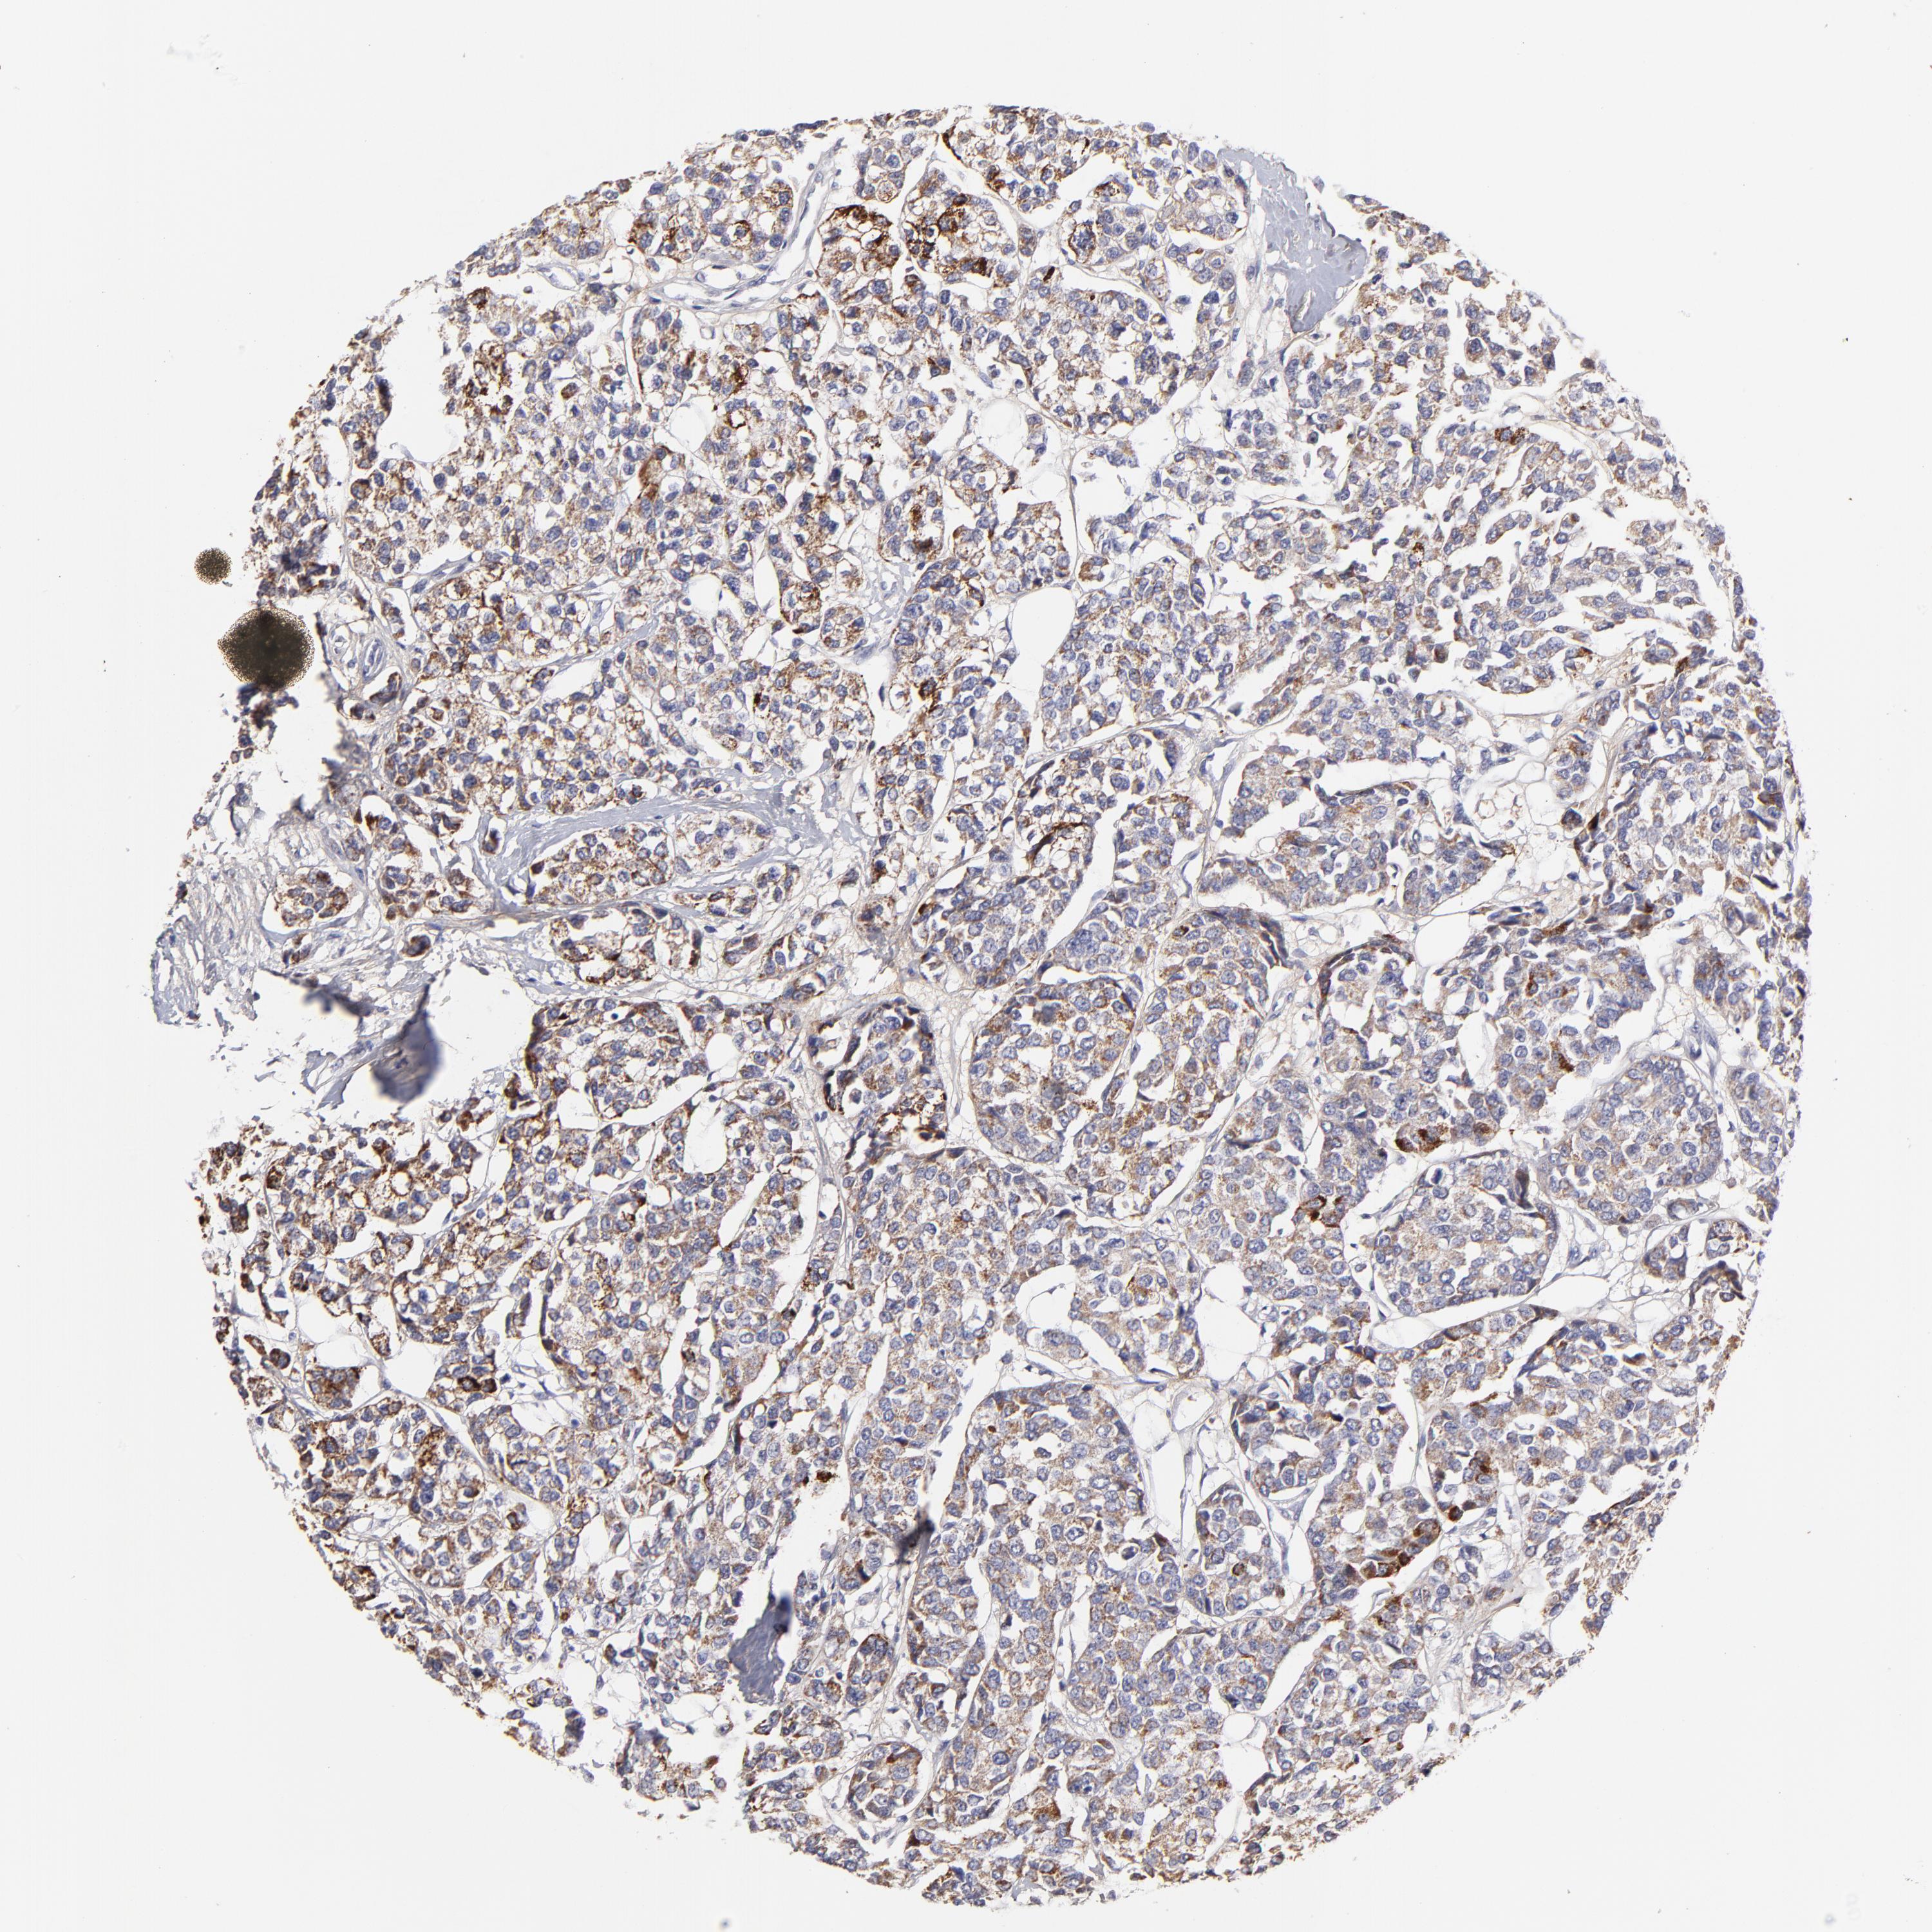

BRCA TCGA BRCA VALIDATION PROTEIN EXPRESSION

ANTIBODIES

AND

VALIDATION